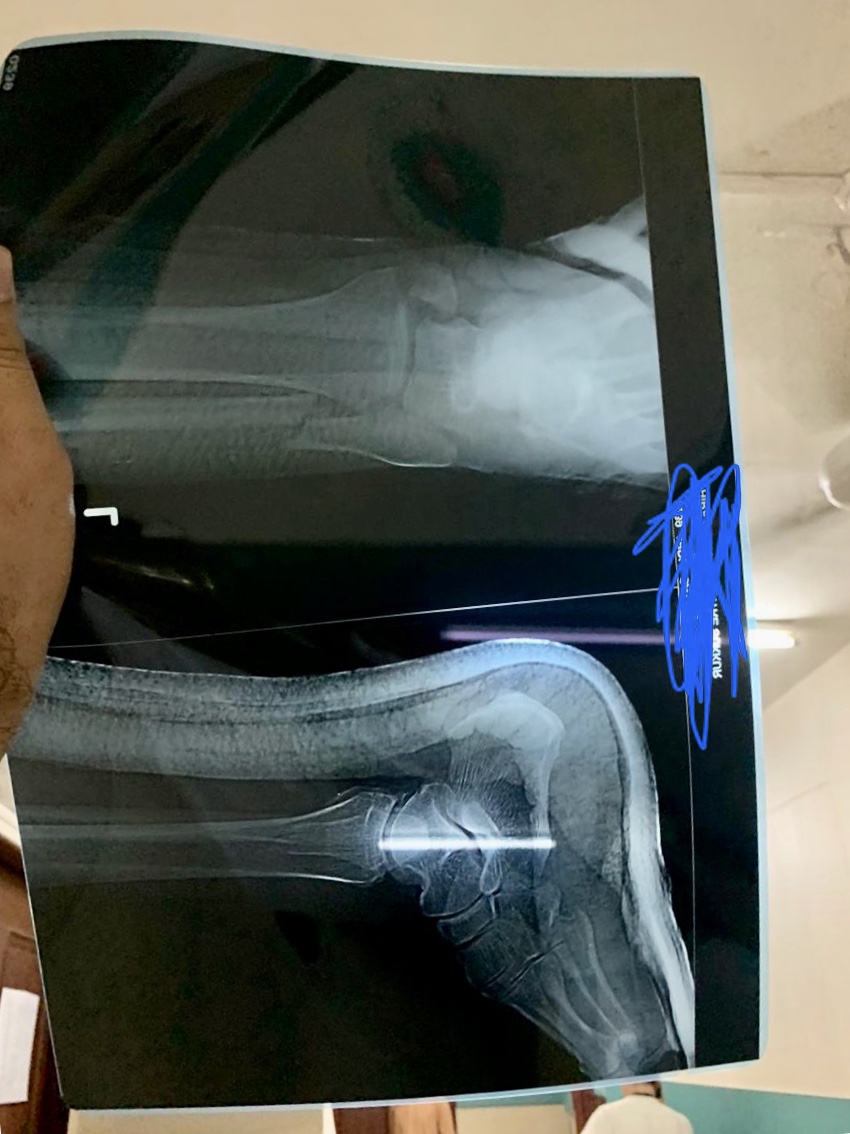

Kindly identify the fractures in the attached X Rays. It was a road Accident. Kindly tell which fractures are present or any other abnormality is there ?

there is a bimaleolar fracture of the ankle need fixation (surgery)

bimalleolar needs surgery.

Bimalleolar be operated ...

It need surgical fixation with screw and plate.....

It’s an ankle fracture which immediately needs surgical procedure.

Yes there are fractures present as seen in X-ray ( bi- malleolar ) plz visit orthopedic surgeon to get the surgical fixation as soon as it is possible..

Bimalleolar frac needs urgent surgery

Bimalleolar ankle fracture,needs surgical fixation only.

it's Pott fracture. needs surgery